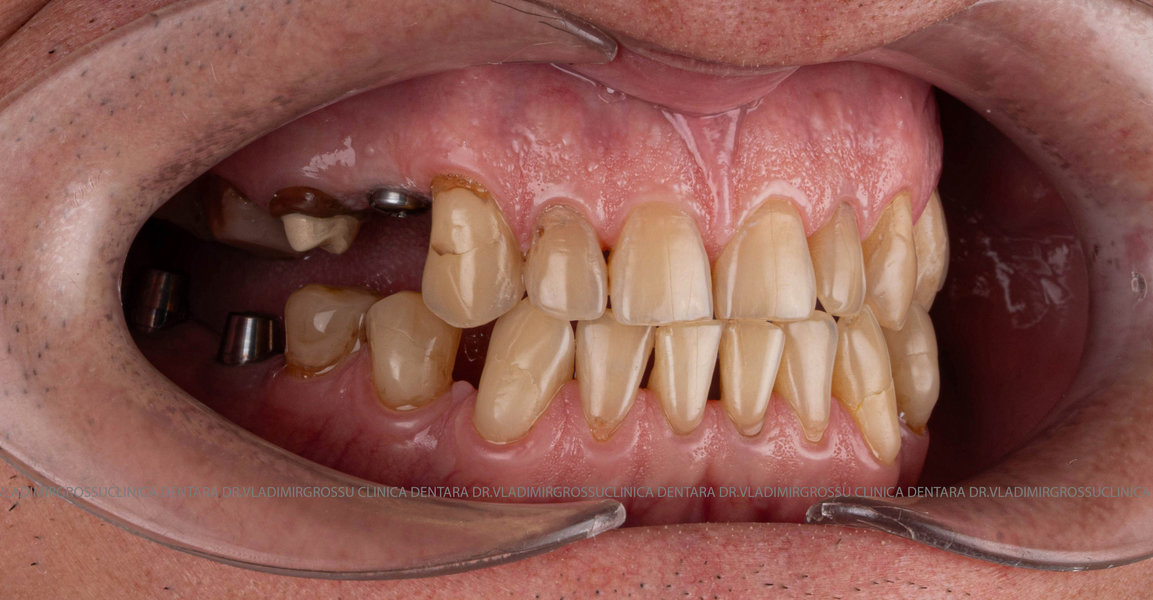

După inserarea unui implant dentar – o rădăcină artificială din titan sau zirconiu –, urmează etapa de protezare, adică atașarea unei structuri protetice (coroană, punte sau proteză) care înlocuiește dintele lipsă.

Etapele protezării pe implanturi

- Consultația inițială și planificarea tratamentului (inclusiv tomografie CBCT)

- Inserarea implanturilor dentare (chirurgie ghidată digital)

- Perioada de osteointegrare (3–6 luni)

- Amprentarea digitală sau clasică a zonei

- Realizarea lucrării protetice (coroană, punte sau proteză)

- Fixarea lucrării și verificarea ocluziei